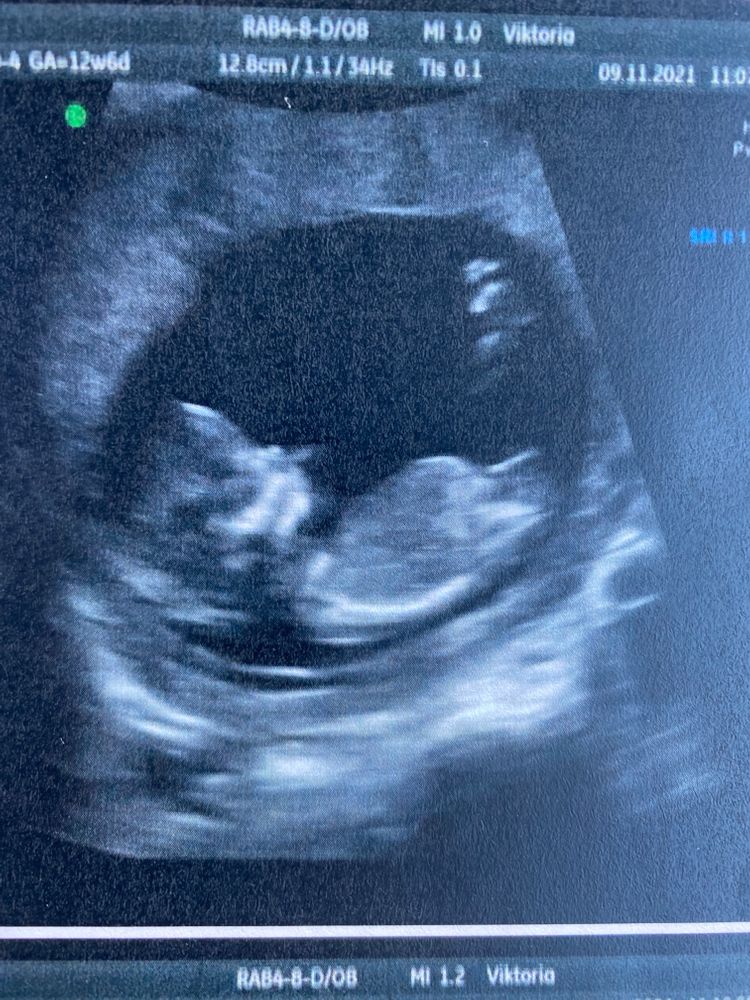

В 12+6 УЗИстка уверенно сказала пол.В 16 и 20 подтвердили.

Опытные УЗИсты на первом скрининге уже видят пол.))

Я в 9(3) сдала кровь для определения пола - девочка. Пришла на первый скрининг 11(6), КТР 12(4). Я говорю, что я уже знаю пол, а мне врач УЗИ молчите ю, молчите, я тоже сейчас скажу- девочка. И вот 💯.